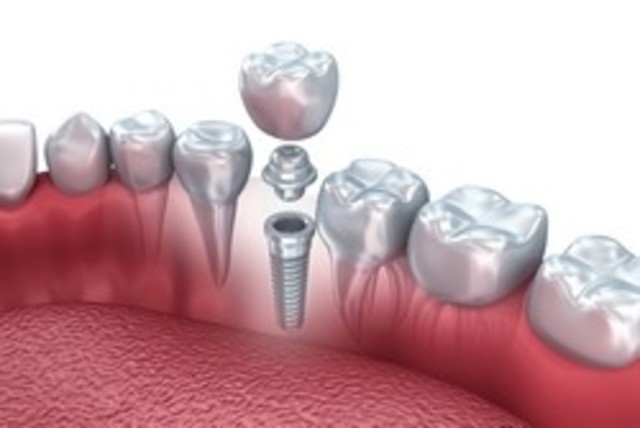

El comienzo de las aplicaciones como la cirugía e implantología guiadas y asistidas por ordenador, introducidas a raíz de los trabajos elaborados en el Proyecto Phidias, comenzado en 1998su difusión mundial, inundándose todo el sector dental con otros productos de los demás fabricantes (i-CAT-ISI, CB-Mercuary-Hitachi, 3D-Accuitomo-JMorita, Picasso-Vatech-Ewoo, Iluma-Kodak, Galileos-Sirona, Planmeca,etc.).